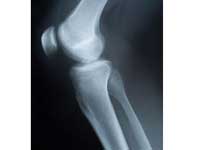

Interlocking Technology Better Than Plaster In Bone Fractures

Saharsa : Instead of the conventional method of treatment by plastering bones in case of fracture, the interlocking of bones technology heals faster and is cost-effective, noted Orthopaedic Surgeon Dr R N Singh informed.

He said in case of fracture in the limb bones, the doctors should adopt interlocking system for treatment of the patient as it is more effective than the conventional system of plastering.

He said through interlocking system the patient recovers within a week whereas in case of plastering the recovery time is nearly three months and sometimes even more.

Dr Singh said apart from being expensive the plasters exert extra pressure on the bones making them fragile and weak.